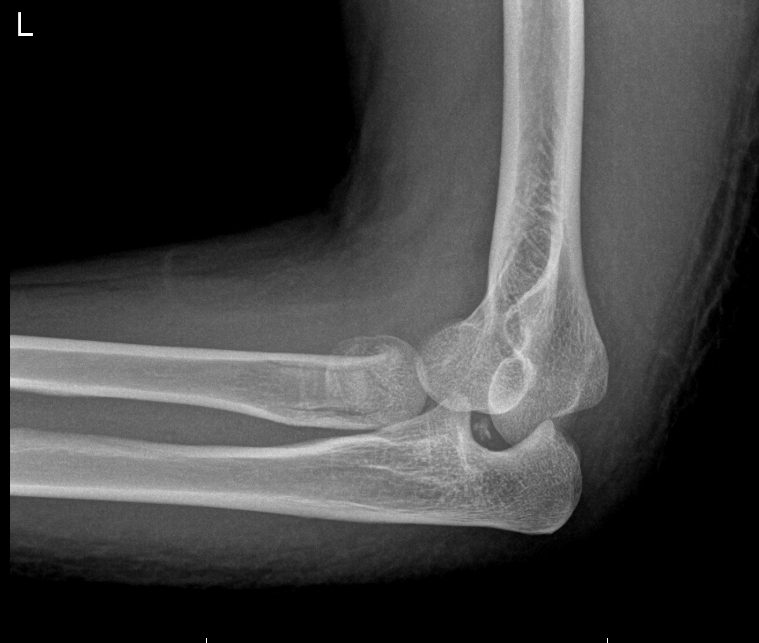

From www.orthobullets.com